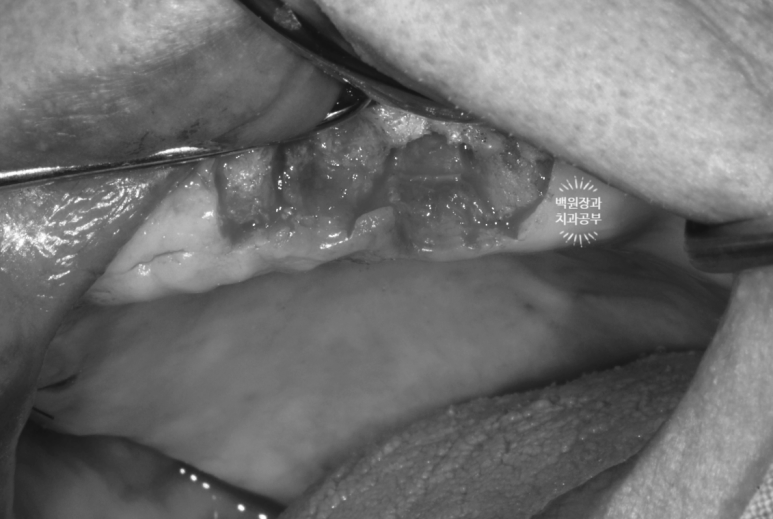

임플란트를 제거할 당시의 사진입니다.

회색으로 보이는 나사선이 임플란트 고정체 (fixture)의 본체이며, '당연히' 뼈 속에 묻혀 있어 보이지 않아야 하는 부분입니다.

수 년간 만성임플란트주위염의 결과로써 치주농양이 형성되었고, 치조골은 사라지고 노출된 임플란트만 남았네요.....

일반적으로, 임플란트 픽스쳐 (fixture)의 50프로 이상 수직골소실이 생기면

제거하고 다시 수술 받으시길 권해드립니다.

깨끗하게 제거하고, 염증 조직을 모두 제거해드린 뒤 깔끔하게 꿰매 드렸습니다.

이렇게 제거한 임플란트만 총 4개 !!!

보면 제거된 임플란트 주변에 뼈는 없고, 염증조직만 가득한 것을 볼 수 있네요...